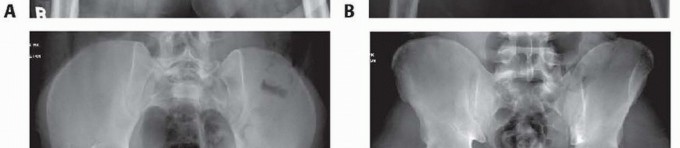

### FIG 2 • Examples of the anatomic variants between genders. The female pelvis has a more concave shape to the ring and the pubic arch has less of an acute angle because of the broader pubic body, as demonstrated in the inlet (A) and outlet (B) views of a female pelvis. The male pelvic ring is more oval, with a much more acute angle anteriorly because of the thinner pubic body, as seen the corresponding inlet (C) and outlet (D) views. Occasionally, lateral compression injuries involve fractures of the pubic rami and a symphyseal disruption. This occurs when the compressed hemipelvis causes the contralateral rami to fracture and the contralateral symphyseal body to tilt inferiorly. Because one side of the symphysis is off and can compress the bladder or uterus, altering the pelvic ring, it should be reduced to the other pubic body, which remains intact.